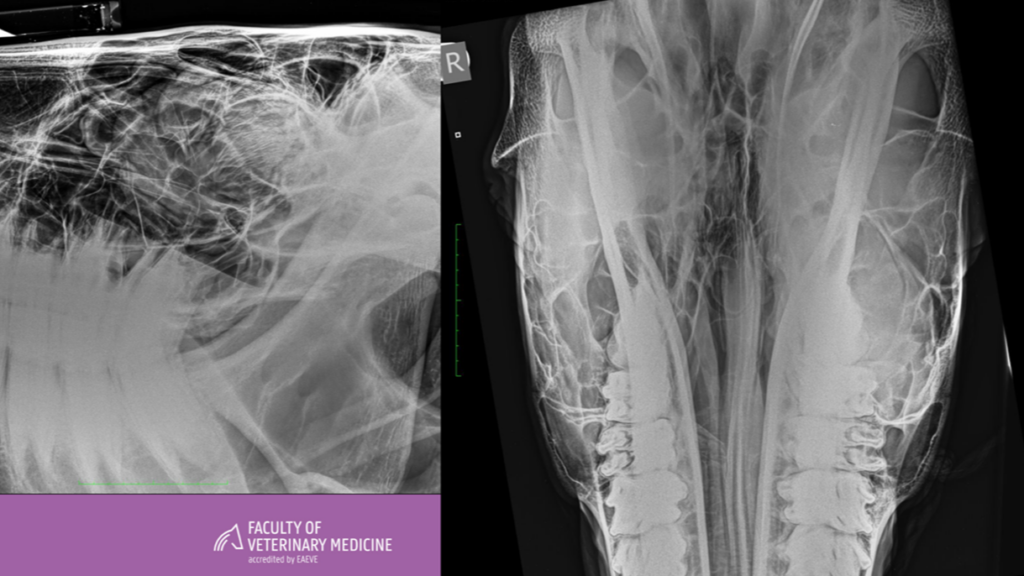

Equine asthma

Anamnese Een 12-jarige ruin van het warmbloedtype wordt aangeboden met de klacht van chronisch hoesten en verminderde prestaties. Zowel in rust als tijdens inspanning valt ademt het paard moeilijk. Het paard staat...